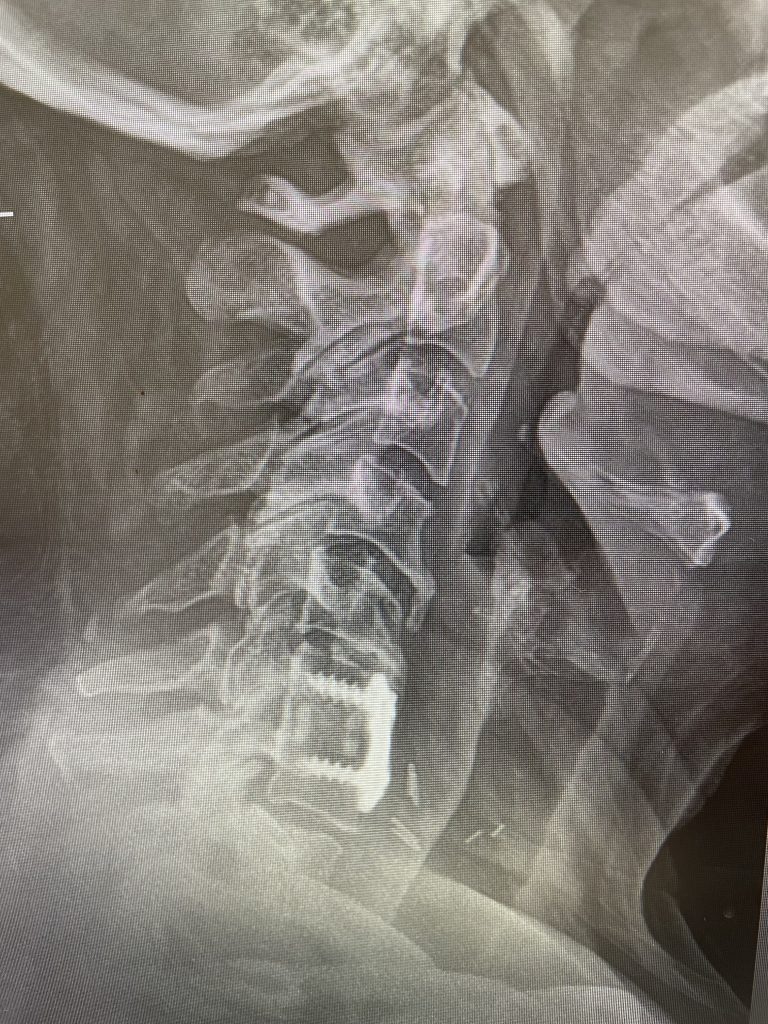

Fig 2: Intraoperative photo showing the thecal sac (arrow)completely decompressed after L3-5 laminectomy. Note the L5 nerve root very well decompressed (asterix)

During the surgery we perform what is called a decompressive laminectomy. Because he had the slip at L4-5 he required a fusion in addition. We elected to use screws with bone graft. People wonder what an actual laminectomy is. A laminectomy is a procedure to remove or “ectomy” the back ring of bone of the spinal segment .You literally bite it away with our special instruments. This bone is called the lamina. You do not need the lamina to live, like an appendix. There are gaps between each lamina segment going up the spine to begin with and there is a tremendous amount of tissue including muscle so one is protected, and it is ok to do this. You need to do the laminectomy to shave away the material that is both hard and soft that is compressing the sac of nerves. Your goal in the surgery is to make the sac nice and round again with a normal diameter. Since in the lumbar spine there is no spinal cord you are dealing with the peripheral nervous system not the central nervous system like the brain and spinal cord. A sac of nerves floating in fluid is a protected system, like a baby in amniotic fluid. At the same time you must not only remove the pressure on the sac, but also you must shave away the pressure on the nerve roots as well, which is called a foraminotomy (Fig 2). The nice thing about a fusion is you can be aggressive in the amount of decompression and joint removal you can do because you are fixing chronic as well as iatrogenic acute instability.